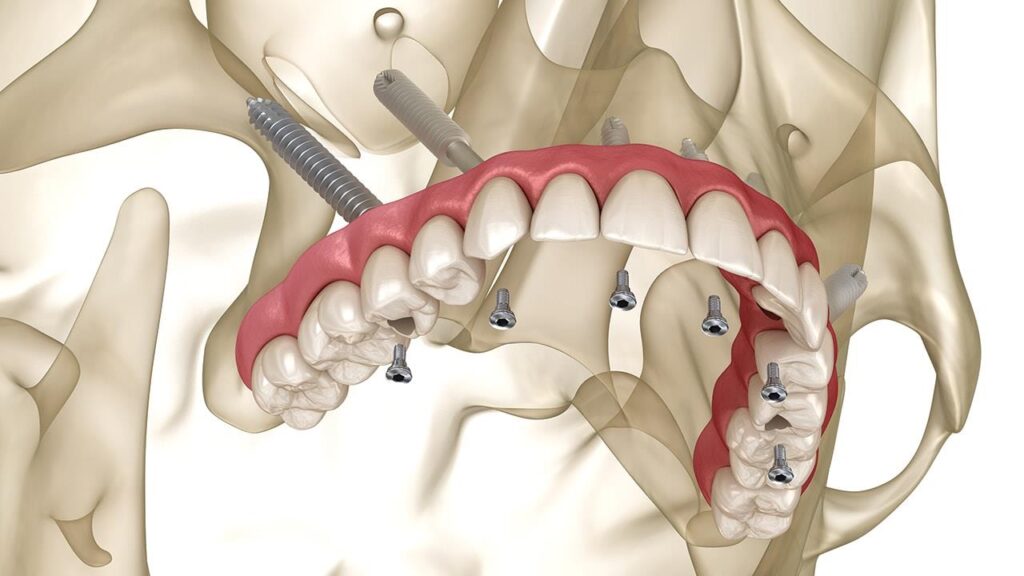

A special type of dental restoration is referred to as zygomatic implants, which are designed for patients with severe maxillary bone loss. These fixtures are surgically placed within the zygomatic bone, commonly known as the cheekbone, unlike conventional implants that are anchored in the jawbone. This alternative approach provides stability when traditional implantation isn’t possible because the bone structure doesn’t allow for conventional implants, and there’s no way to place them due to inadequate bone support. This allows for the creation of a stable foundation for the Dental prosthesis without any requirement of bone grafting. These implants are longer than traditional dental implants.

- Surgical placement – the surgery is performed under general anaesthesia or under local anesthesia. The type of Anesthesia depends on the patient’s and surgeon’s comfort ability. The surgeon makes small incision in the gum tissue and carefully dissect to reach the bone and places the zygomatic implants into the cheekbone. It is placed in a planned angulation and depth. In complicated cases a surgical guide is utilized to place the Implants.In many cases a temporary processes can be loaded immediately allowing you to leave the clinic with a full functional smile.